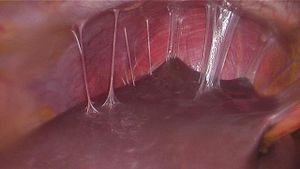

Fitz-Hugh-Curtis syndrome

- A complication of Pelvic Inflammatory Disease, involving acute gonococcal or chlamydia trachomatis peritonitis of the right upper quadrant in women

- Pain is caused by liver capsule inflammation